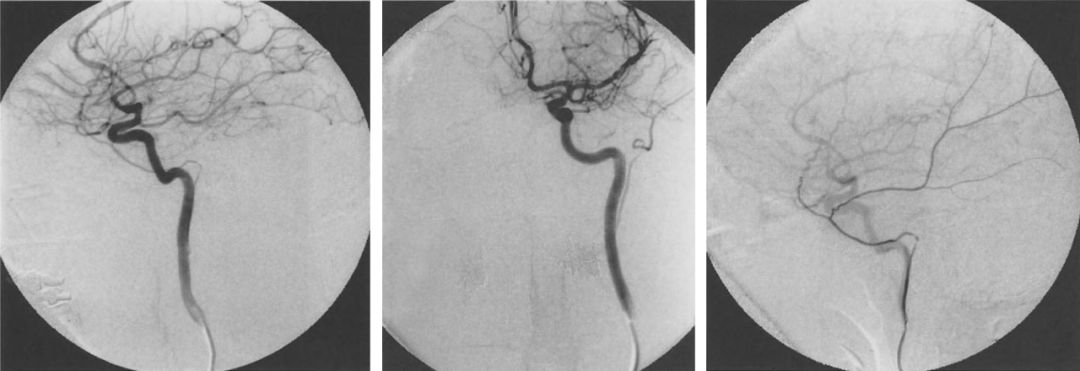

Lasjaunias报道了一例(Lasjaunias, 2001b)。颈内动脉造影正位(A)和侧位(B),咽升动脉造影侧位(C)。咽升-鼓室-镫骨动脉变异。咽升动脉发自颈段颈内动脉,向上通过鼓室。脑膜中动脉发自咽升动脉。

![]()